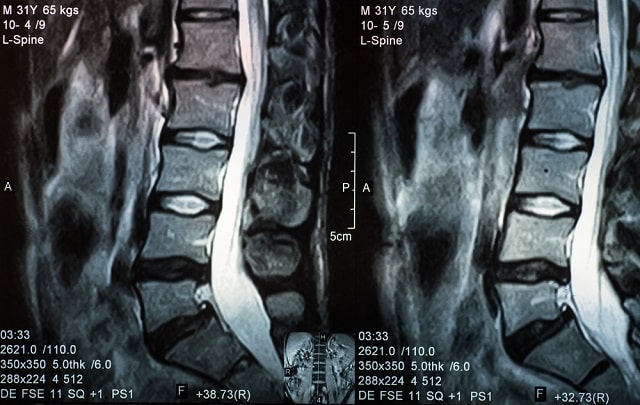

Протрузия межпозвоночного диска - это износ тканей, вследствие чего они увеличиваются в размере и выходят за пределы своего естественного положения. Из-за этого задевается близлежащие нервы и возникает боль. Снижается подвижность позвоночника. По ссылке можно уточнить, сколько стоит лечение протрузий дисков в Харькове, а ниже рассмотрим, как образуется протрузия диска, какие при этом симптомы и какую делают профилактику.

- Когда увеличенное пульпозное ядро еще располагается в фиброзном кольце, но уже заходит на канал позвоночника – это протрузия.

- Когда фиброзное кольцо повреждено и ткани выходят за его пределы, ставят диагноз грыжа межпозвоночного диска.

В зависимости от места расположения протрузия может быть латеральной, то есть находиться в боковой части позвоночника. Задние латеральные протрузии встречаются чаще всего. Выбухание диска происходит назад и в бок в отношении позвоночного столба. В таком случае появляется интенсивное воздействие на корешки нервных путей. Если протрузия направлена к центру канала спинного мозга, не проявляется острых симптомов и боли. При задних протрузиях выбухание диска воздействует на отделы спинного мозга и нервных корешков, которые отвечают за чувствительность и моторику ног и органов малого таза. Задать интересующие вопросы о протрузиях можно по ссылке (медицинский центр доктора Бубновского).